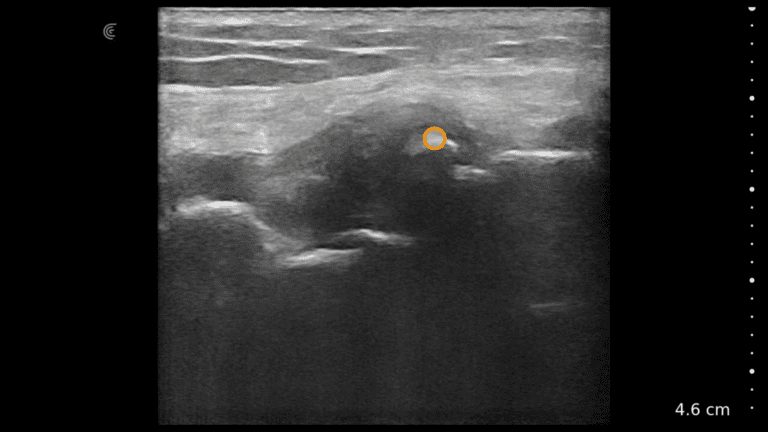

Dr. Ines Verner demonstrates how to visualize the facial, superior and inferior labial arteries. High-definition vascular imaging using Color Doppler allows her to visualize the locations and avoid intervascular injections.